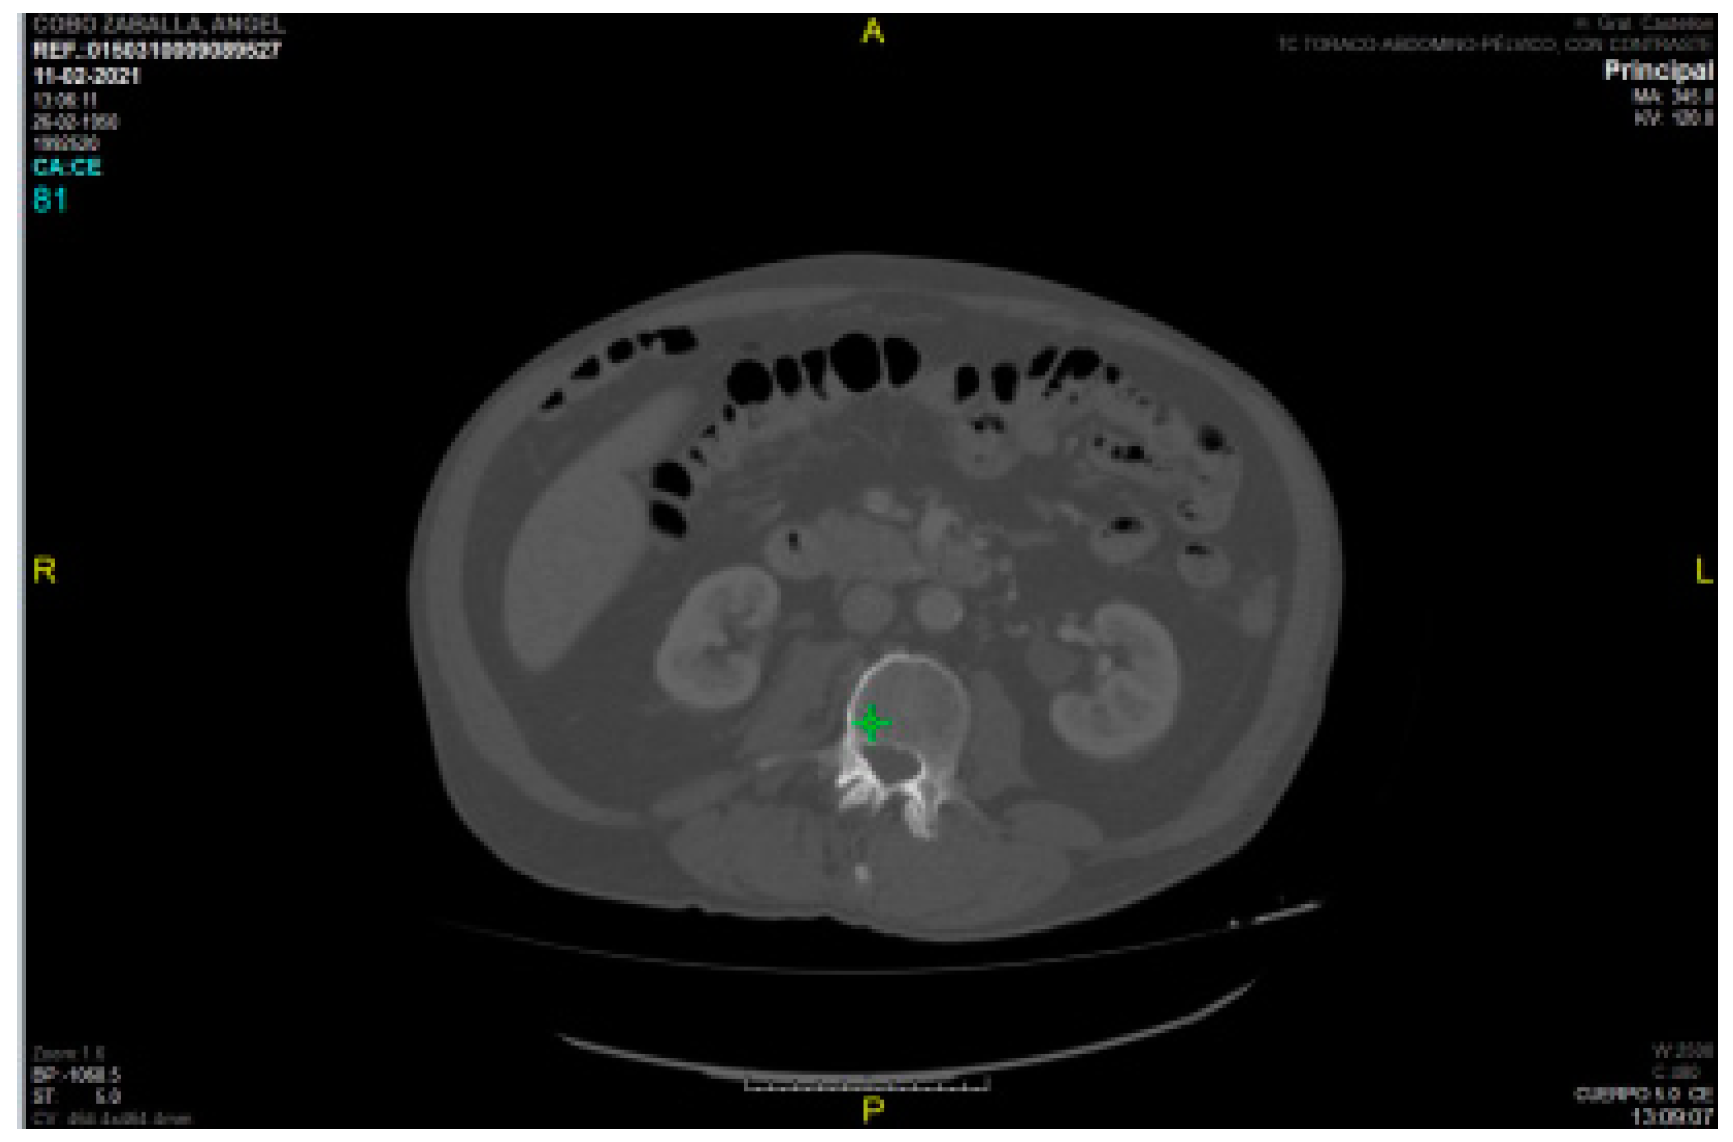

Regarding intramuscular fat mass, in the present study there is a lack of correlation between myosteatosis measured in HU density on CT compared to adipose tissue depth measured by rectus femoris ultrasonography (PMI r -0.040 and SMI r -0.133) and rectus femoris muscle echogenicity (r -0.075 and r 0.118 for SMI and PMI, respectively). This may be due to the method used (with Centricity Universal Viewer v7.0 SP1 0.3), which is a manual method and therefore the HU density varies depending on the amount of contrast used, as can be seen in the two figures (

Figure 7. HU density PMI 70 /

Figure 8. HU density -52).

This is in contrast to semi-automated methods (4) where the use or non-use of contrast does not affect the results.